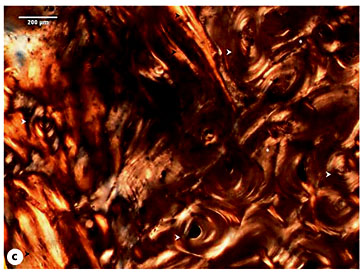

With regard to the Sk. 119 rib callus, no evidence of a cortical bone break was observed. Actually, the cortex exhibited a mature structure composed of numerous rows of osteons and interstitial lamellae. In the upper and lower edges of the pleural surface, a clear separation between the cortical bone and the patches of periosteal new bone was noticed. This level of microstructural organization was clearly distinguishable from the mesh-like pattern of interconnected lamellae and amorphous new bone formation noticed on the central portion of the pleural surface. Moreover, an accumulation of new bone in distinct stages of maturation was also observed. For instance, the deepest layers were formed by densely packed lamellae with small, elongated and erratic osteocyte lacunae, whereas the outermost ones were composed of a random structure with an immature appearance and were densely populated by circular osteocyte lacunae (fig. 11a-c1).

a Micrograph of the Sk. 119 right rib showing the cortical tissue composed of mature osteons (white arrowheads) and interstitial lamellae. A clear separation between the periosteal circumferential lamellae and a more disorganized periosteal new bone formation (white asterisk) is visible. b Segment exhibiting several rows of osteons (white arrowhead) intersected by sheets of lamellar bone with variable density (black arrowheads). Note the presence of a lumpy deposit of periosteal new bone (white asterisks). c Periosteal new bone formation exhibiting several degrees of bone organization (black arrowheads; circle 1). Multiple osteons are visible at the cortical level (white arrowhead). c1 Detail of the previous figure showing the inner layers composed of well-defined lamellae with small and elongated osteocyte lacunae and the outmost layers with a general lack of bone organization and populated by large and rounded osteocyte lacunae. Polarized light. Magnification ×40; ×100.

a Micrograph of the Sk. 119 right rib showing the cortical tissue composed of mature osteons (white arrowheads) and interstitial lamellae. A clear separation between the periosteal circumferential lamellae and a more disorganized periosteal new bone formation (white asterisk) is visible. b Segment exhibiting several rows of osteons (white arrowhead) intersected by sheets of lamellar bone with variable density (black arrowheads). Note the presence of a lumpy deposit of periosteal new bone (white asterisks). c Periosteal new bone formation exhibiting several degrees of bone organization (black arrowheads; circle 1). Multiple osteons are visible at the cortical level (white arrowhead). c1 Detail of the previous figure showing the inner layers composed of well-defined lamellae with small and elongated osteocyte lacunae and the outmost layers with a general lack of bone organization and populated by large and rounded osteocyte lacunae. Polarized light. Magnification ×40; ×100.

Despite the morphology of the outer shell of the Sk. 119 rib callus, which resembles a consolidated fracture, the histological study showed an unremodeled architecture compatible with a subperiosteal hematoma eventually caused by periosteum detachment, bleeding, and new bone formation through activation of the osteogenesis process. Nevertheless, a case of an incomplete microfracture cannot be completely excluded from the present diagnosis. The microstructure of hematoma is variable, ranging from thin layers that resemble a slip-like cover to relatively short, bulky bone trabeculae with extensive bridging, arc-like formation, and/or multiple layers [35,36,37]. In the case under discussion, the presence of tissues in distinct stages of maturation: immature and more disorganized bone/isodiametric osteocyte lacunae (outer layers) and lamellar bone/flattened osteocyte lacunae (deepest layers) seem to indicate that the bone lesion was undergoing remodeling at the time of death. Little can be said about the elapsed time after hematoma formation; nevertheless, and during fracture repair, the remodeling of woven bone into longitudinally oriented lamellar bone is observed to occur 14-21 days after injury [48]. Independently of the diagnosis, the presence of 9 rib calluses (n = 6, right ribs; n = 3, left ribs; table 2) seems to indicate that this female was exposed to chest trauma that caused a minor tissue disruption in the 9th right rib.